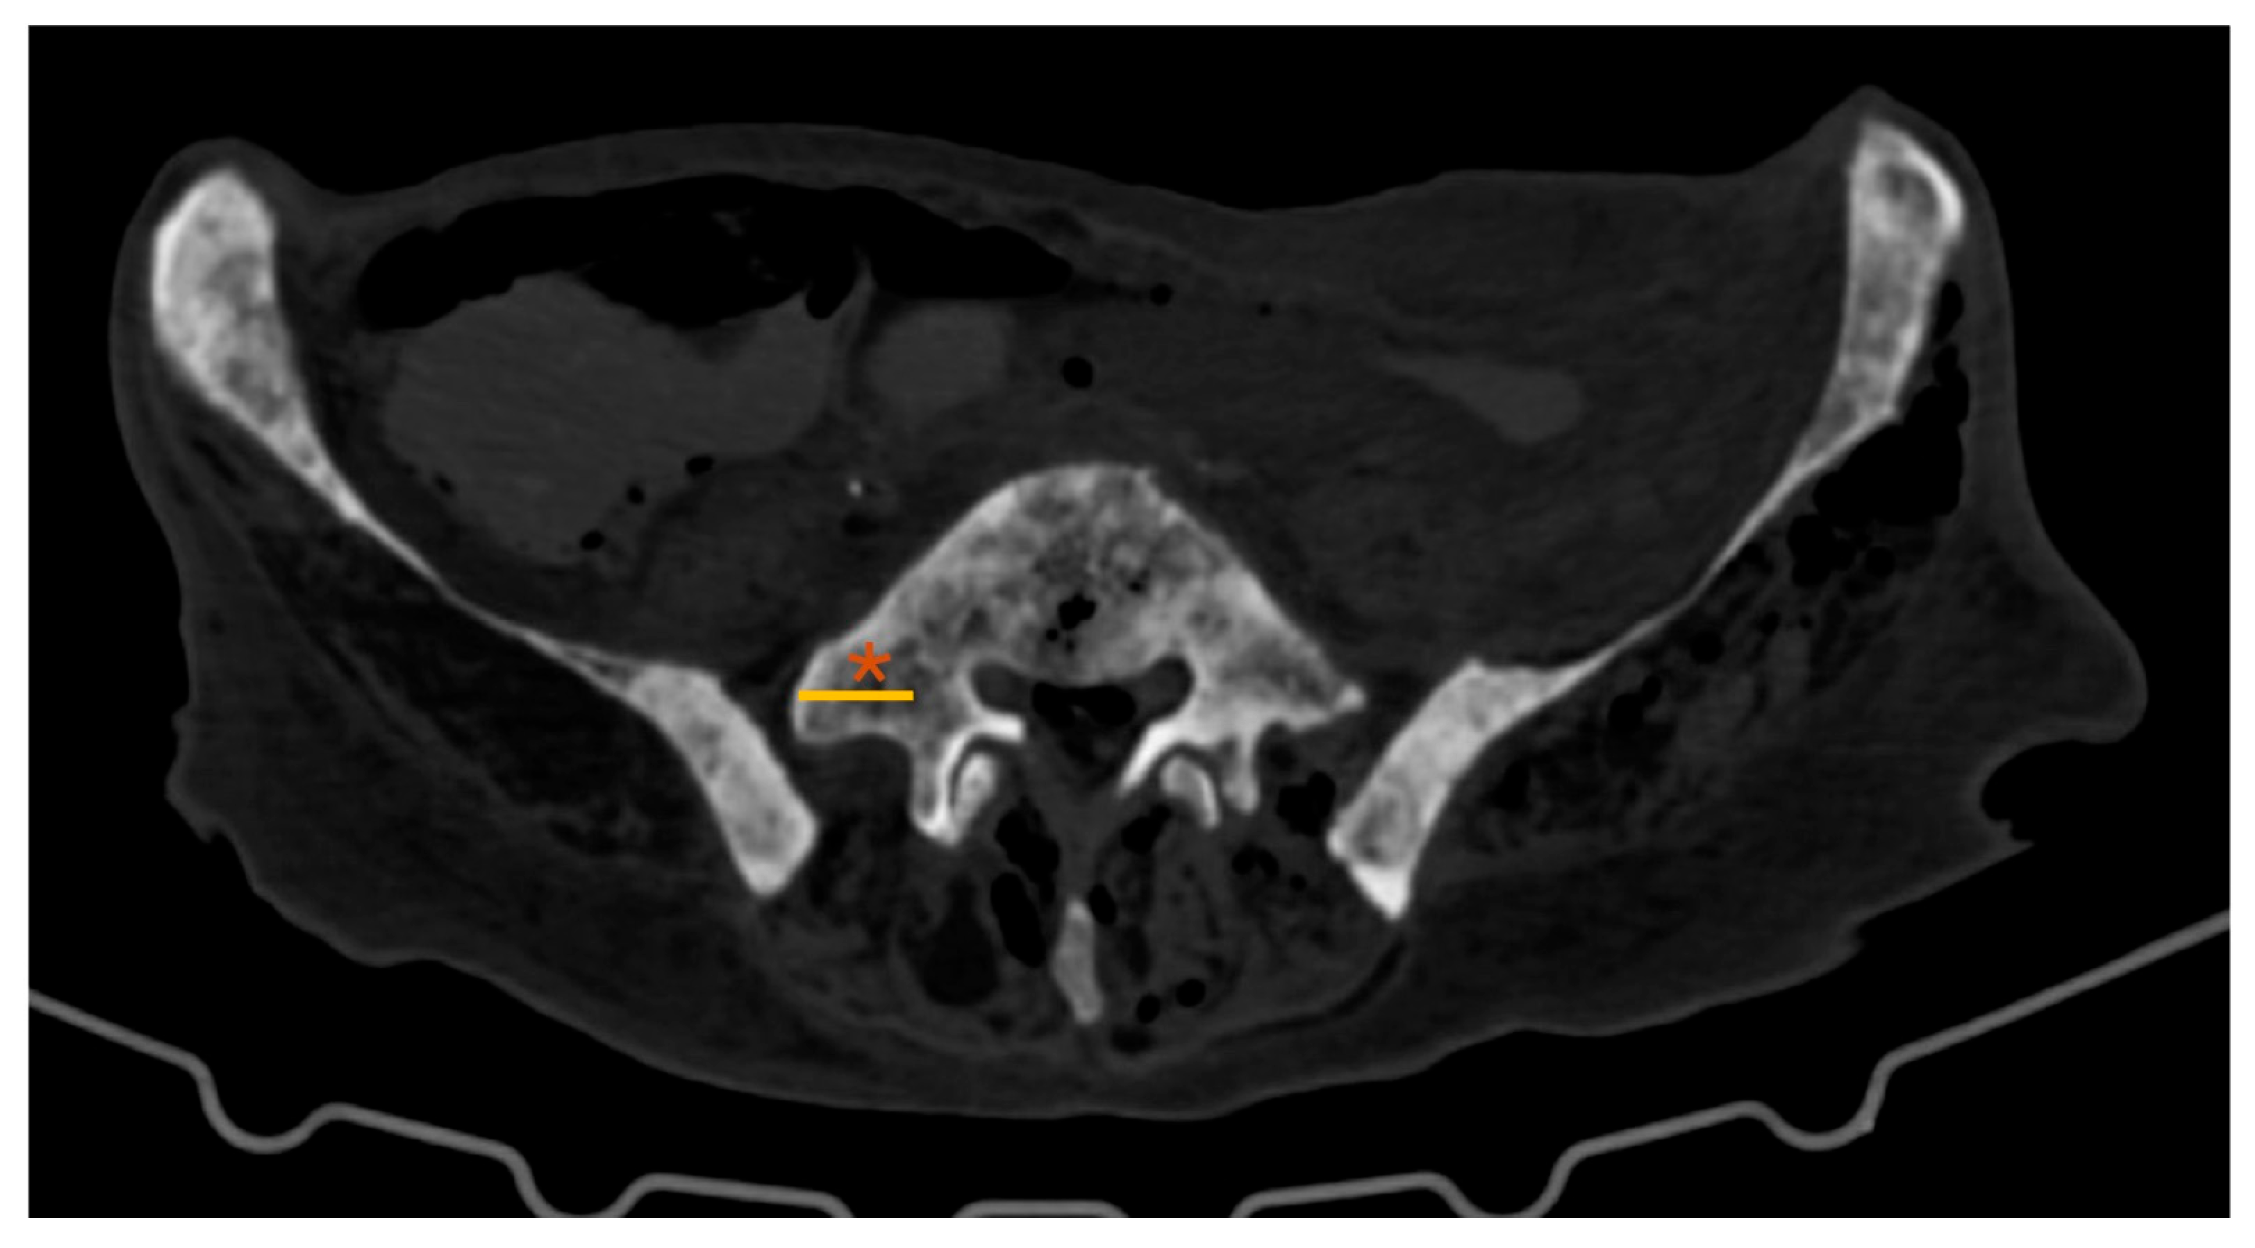

• L5-TP: length of the L5 TP (axial plane; Figure 2)

CT-based L5-TP (Figure 2) closely matched the anatomical A-B distance, with no significant differences (p=0.144). However, the values obtained in the CT analysis were slightly higher.

Figure 2. Lumbar spine CT – axial plane; *: L5 transverse process; yellow line: L5 transverse process length.